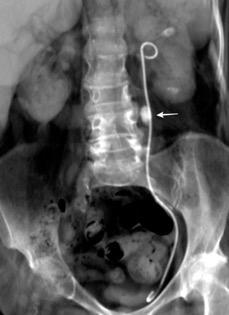

27. DERRAME PLEURAL IZQUIERDO. URINOMA

Enfermedad subdiafragmática Urinoma

Raro. Trasudado.

Orina en espacio pleural

Causas en 78 casos

Trauma……..66

Postcirugía 16

Obstrucción…21 aguda con cálculo e hidronefrosis..12

Freitas A et al. Pleural Effusion Secondary to Obstructive Uropathy: A Case of Urinothorax. Eur J Case Rep Intern Med. 2020/ Toubes ME et al. Urinothorax: a systematic review. J Thorac Dis 2017;

Hidronefrosis con cálculo ureteral